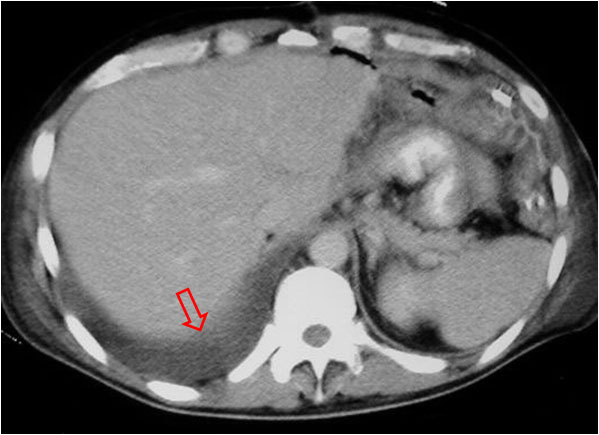

Este signo nos permite diferenciar entre derrame pleural y ascitis en un estudio de TC. Cuando existe una interfase nítida entre líquido y el hígado o el bazo, se trata de ascitis; cuando la interfase no es nítida, se trata de derrame pleural (flecha). El derrame pleural ocupa una posición más posterior y medial, mientras que la ascitis se localiza anterior y lateral al hígado y al bazo.

Esta segunda imagen corresponde a ascitis. Observa como la interfase entre el bazo y el líquido (flecha) es más nítida que en la imagen anterior. También lo es la interfase entre el hígado y el líquido.